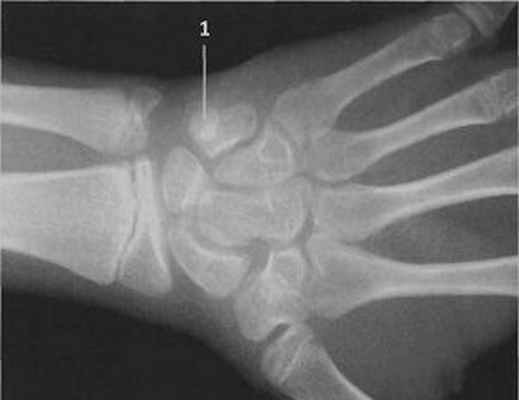

Пациент обратился на консультацию с жалобами на образование на кончике 2-го пальца правой кисти. Появление образования было связано с порезом 4 месячной давности с последующим медленным заживлением и периодическим инфицированием в ходе привычной повседневной деятельности. После заживления пациент отметил появление плотного образования под кожей. Периодически пациент отмечал появление покраснения и чувства распирания в связи с механическим воздействием, которые постепенно самостоятельно стихали. Пациент самостоятельно применял наружные заживляющие средства – без выраженного эффекта. Нарушения общего самочувствия за указанный период не отмечал. Рентгенологическое исследование показало признаки мягкотканного образования и отсутствие изменений кости дистальной фаланги.

Во время эксцизионной биопсии было выявлено плотное, округлое, четко отграниченное от окружающих тканей, розовое образование диаметром 4 мм. Основание опухоли было обращено к кости дистальной фаланги. Гистологический анализ: нодулярный теносиновит. Появление нодулярного теносиновита (или гигантоклеточной опухоли сухожильных влагалищ в терминологии иностранных коллег) на дистальной фаланге — довольно редкая ситуация для этой опухоли.